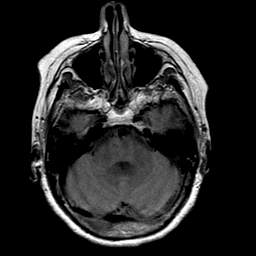

Stroke: proton density-weighted MR #1 -- Slice #6

[Home][Help][Clinical] Slice 6